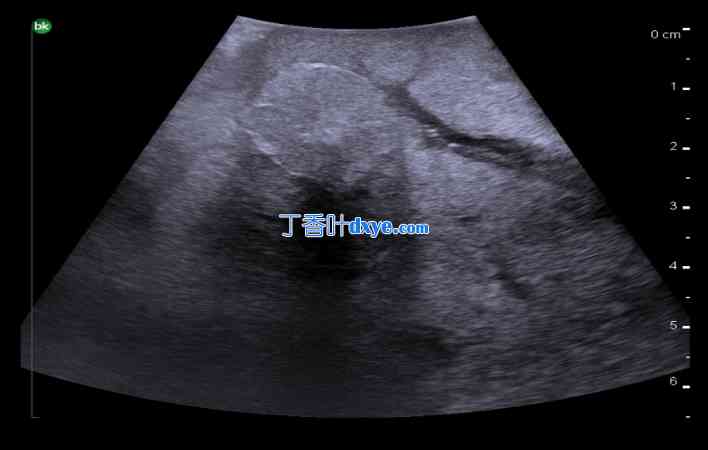

术中肝实质超声图像。a) 正常肝实质(频率 10 MHz)、b) 肝脂肪变性(频率 10 MHz)、c) 肝硬化(频率 5 MHz)。

34.jpg